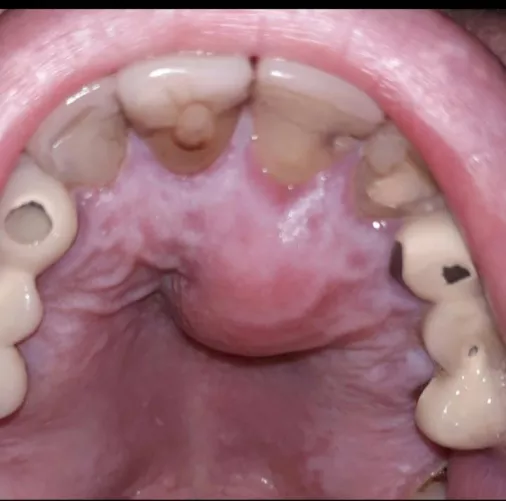

Abscess roof of mouth followed root canal  by Sea_Pangolin3840

HD Abscess roof of mouth followed root canal